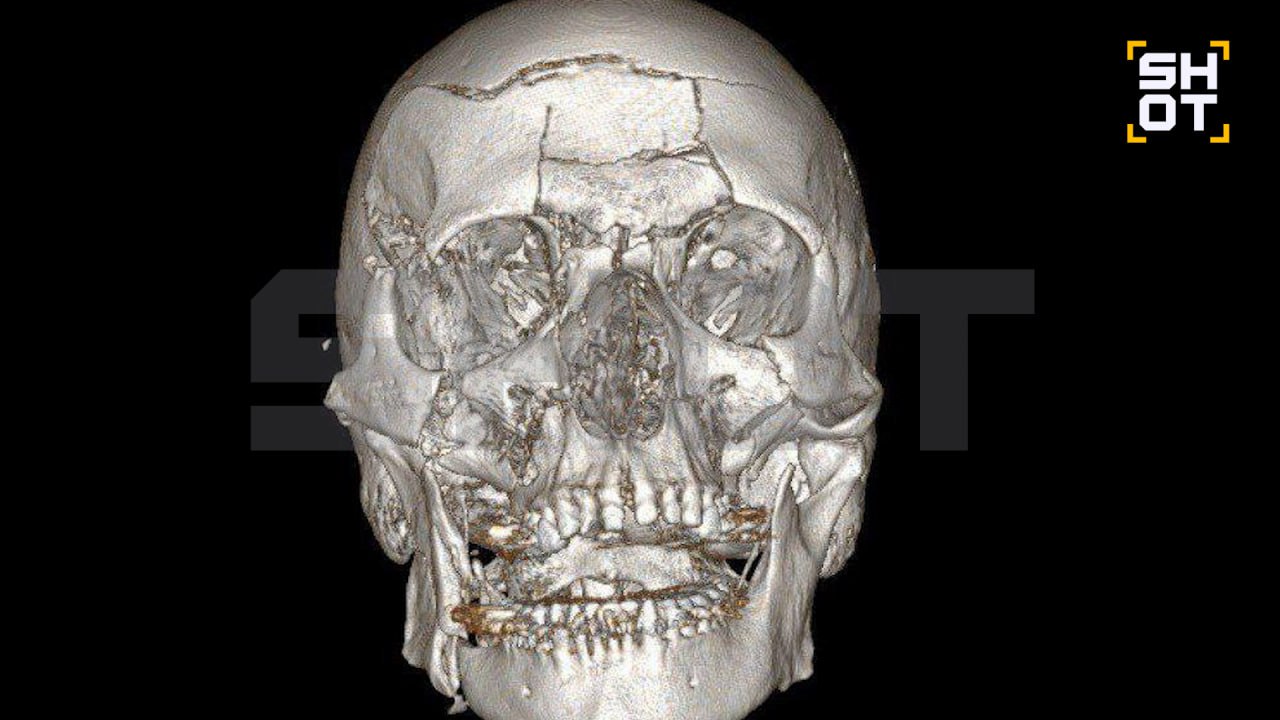

В подмосковном Жуковском произошёл тяжёлый несчастный случай, в результате которого 44-летний мужчина получил множественные травмы лица. По информации источника, он упал со снегохода, что привело к серьёзным повреждениям лобной кости, носовых пазух и челюсти.

Для спасения жизни пострадавшего в Жуковской больнице была проведена сложная операция, которая длилась семь часов. В ходе вмешательства нейрохирурги удалили обломки лобной кости, а также заднюю стенку пазухи и слизистую оболочку. Просвет пазухи был заполнен аутокостной крошкой.

Челюстно-лицевые хирурги восстановили повреждённые участки черепа, включая лоб, глазницы и обе челюсти. Для фиксации использовались титановые мини-пластины. После операции мужчина прошёл первичную реабилитацию и был выписан из больницы. Однако его ждёт длительный период восстановления.